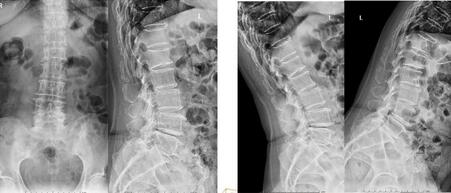

?。?、王某,男,33歲,因“腰腿痛11月加重5天”入院,無明顯外傷史,有外院診治史?;颊哂谌ツ?月份無明顯誘因出現(xiàn)腰腿痛,疼痛向臀部及左下肢放射,曾去年9月至某醫(yī)院就診,CT提示:腰椎間盤突出(L4-L5左旁中央型)。于5天前抱小孩時(shí)癥狀再次加重,伴有左下肢麻木。行走不能,于甘露醇、地塞米松、理療+牽引等保守治療,未見明顯療效。遂于今日來我院就診,門診擬“腰椎間盤突出癥”收住入院。

3.輔助檢查:CT(外院)顯示L4-L5椎間盤突出左旁中央型。

初步診斷:據(jù)患者病史,癥狀,體征及影像學(xué)檢查,腰椎間盤突出診斷基本明確;不排除合并椎管狹窄,MRI進(jìn)一步檢查。

4.輔助檢查:MRI顯示腰椎退行性變:L4-5椎間盤脫出(左側(cè)隱窩型),伴左側(cè)側(cè)隱窩狹窄,相應(yīng)神經(jīng)根受壓,馬尾神經(jīng)受壓;局部腰椎管狹窄。

診斷結(jié)果:根據(jù)患者病史、癥狀、體征及輔助檢查,目前診斷明確?,F(xiàn)患者腰腿痛明顯,伴有脊髓神經(jīng)根受壓、椎管狹窄癥狀,保守治療不能緩解,如不進(jìn)行手術(shù),壓迫癥狀會進(jìn)一步加重,甚至造成截癱。

手術(shù)方案:全麻下行“腰椎間盤摘除+腰椎管減壓植骨融合內(nèi)固定術(shù)”。取腰背部后正中縱行入路;骨膜下剝離椎旁肌,椎管減壓、植入椎弓根螺釘,保護(hù)脊髓及神經(jīng)根,摘除髓核,搔刮終板、椎間植骨并安置融合器;抱緊、安裝椎弓根螺釘、棒系統(tǒng);嚴(yán)密止血、放置引流、關(guān)閉切口。